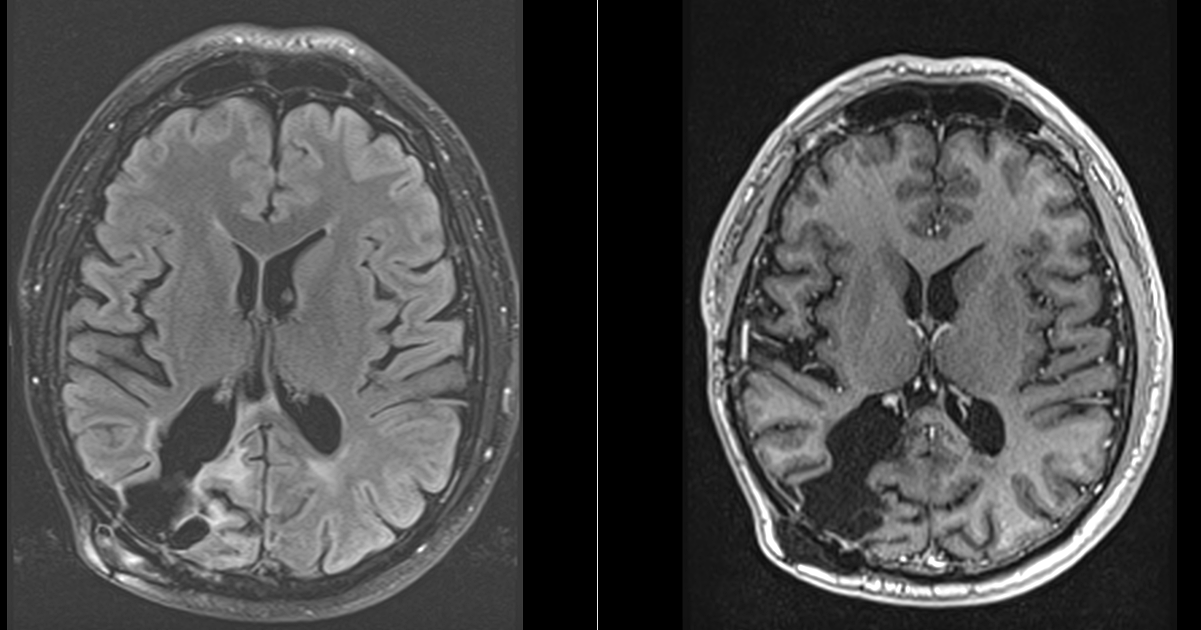

Controalele imagistice s-au repetat periodic, fiecare RMN fiind un moment de emoție și speranță.

Astăzi, la 9 ani de la operație, nu există semne de recidivă tumorală. Deficitul vizual s-a stabilizat, iar dificultățile de recunoaștere a fețelor s-au ameliorat parțial. Mai important însă, pacientul și-a recâștigat viața de zi cu zi.